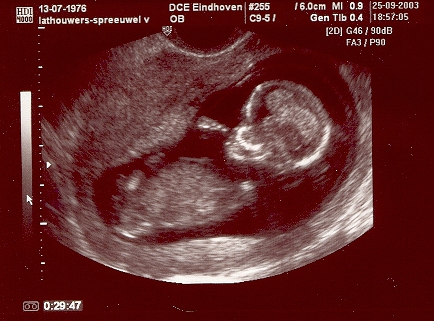

Woensdag 26 november 2003

Jouw dagboek begint vandaag. Mama is nu 21 weken zwanger van jou en wordt er nu een “pretecho” gemaakt door Francette Poos (een zeer kundige echoscopiste). Papa en mama zijn erg benieuwd naar jou, groei je goed, is alles goed ontwikkeld, enz. Mama wil heel graag jouw hartje zien. Helaas heb je een verkeerde ligging en kunnen we jouw hartje niet zien. Wel klopt jouw hartje erg goed. Gelukkig mogen we terug komen om naar jouw hartje te kijken. Op een of andere manier wil mama dit erg graag zien. In onze nabije omgeving is iemand zwanger van een kindje met een hartafwijking. Dat maakt mama een beetje ongerust. Op maandag 8 december mogen wij terug komen voor een nieuwe echo.

Maandag 8 december 2003

Vandaag een korte afspraak voor de “pretecho”. Jouw hartje wordt nagekeken. Er wordt uitgebreid gekeken, maar helaas is jouw hartje niet goed ontwikkeld en moeten we naar het ziekenhuis.